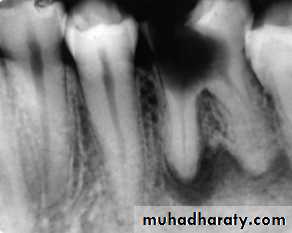

Radiographic features:

Initially, No radiographic change.

With progression, slight widening of PDL, lamina dura may become less defined.Histopathological features:

Most lesions are discovered on routine radiographic examination.A well-defined radiolucency of bone apical to the offending tooth. Loss of the apical lamina dura.

The lesion may be circumscribed or ill defined.

The size is variable.